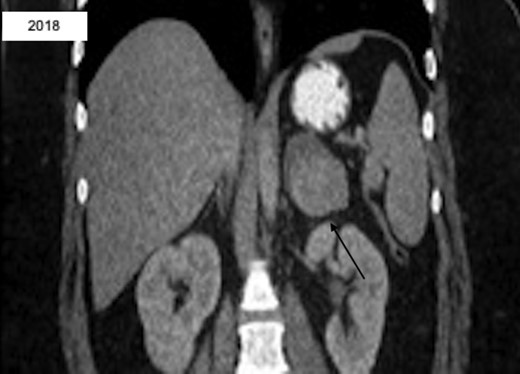

A 27-year-old Caucasian female with a past medical history significant for untreated hypertension, irritable bowel syndrome, hidradenitis, and ovarian cysts presented to the emergency department for evaluation of a three-day history of left flank pain. She had a prior CT scan seven years prior at which time a 2.7 × 2.1 cm left adrenal lesion, consistent with an adenoma, was found (Fig. 1). At recent presentation, non-contrast CT scan of the abdomen and pelvis was performed, demonstrating a 5.6 × 3.7 × 4.0 cm mass contiguous with the left adrenal gland and splenic artery (Fig. 2). She was ultimately discharged home with recommendation for further outpatient workup. Subsequent CT of the abdomen and pelvis with IV contrast revealed a 5.0 × 6.2 cm left adrenal mass. Portal phase density was 67 HU with washout seen at 15 minutes with HU of 42. MRI of the abdomen with adrenal protocol was then performed, depicting a 4.7 × 5.9 cm enhancing left adrenal mass with a differential diagnosis of pheochromocytoma, adrenal carcinoma, and metastatic disease. Biochemical workup was unremarkable aside from an elevated total/free testosterone of 124 ng/dl and 17.2 pg/ml. However, a diagnosis of polycystic ovarian syndrome was discussed with her in the past. The patient was then seen in the surgical oncology clinic at which time she complained of persistent left flank pain with no abnormal findings on physical examination. Surgical resection was recommended and patient underwent a robotic assisted laparoscopic left adrenalectomy. She had an uncomplicated post-operative course and was discharged home the following day. Surgical pathology revealed a high grade ACC measuring 8.4 cm in greatest dimension. There was invasion into the adrenal capsule and presence of small vessel lymphovascular invasion. Surgical margins were uninvolved with distance to closest radial margin of one mm. Immunostain showed significantly elevated Ki-67 labeling index up to 30% in focal areas of the tumor. The tumor also showed focal mitotic activity ranging from 0-4 mitoses/HPF, resulting in a diagnosis of high grade ACC. This case was discussed at a multidisciplinary meeting and adjuvant treatment was recommended. She then received external beam radiation to the left adrenal bed with a total dose of 5040 cGy at 180 cGy/F. She established care with medical oncology and was started on Mitotane with a goal dose of 6000 mg/day and goal level of 14-20 mcg/mL.

CT abd/pelvis revealing interval enlargement with heterogeneous density, now 5.0 × 6.2 cm with eccentric hyperdense region.